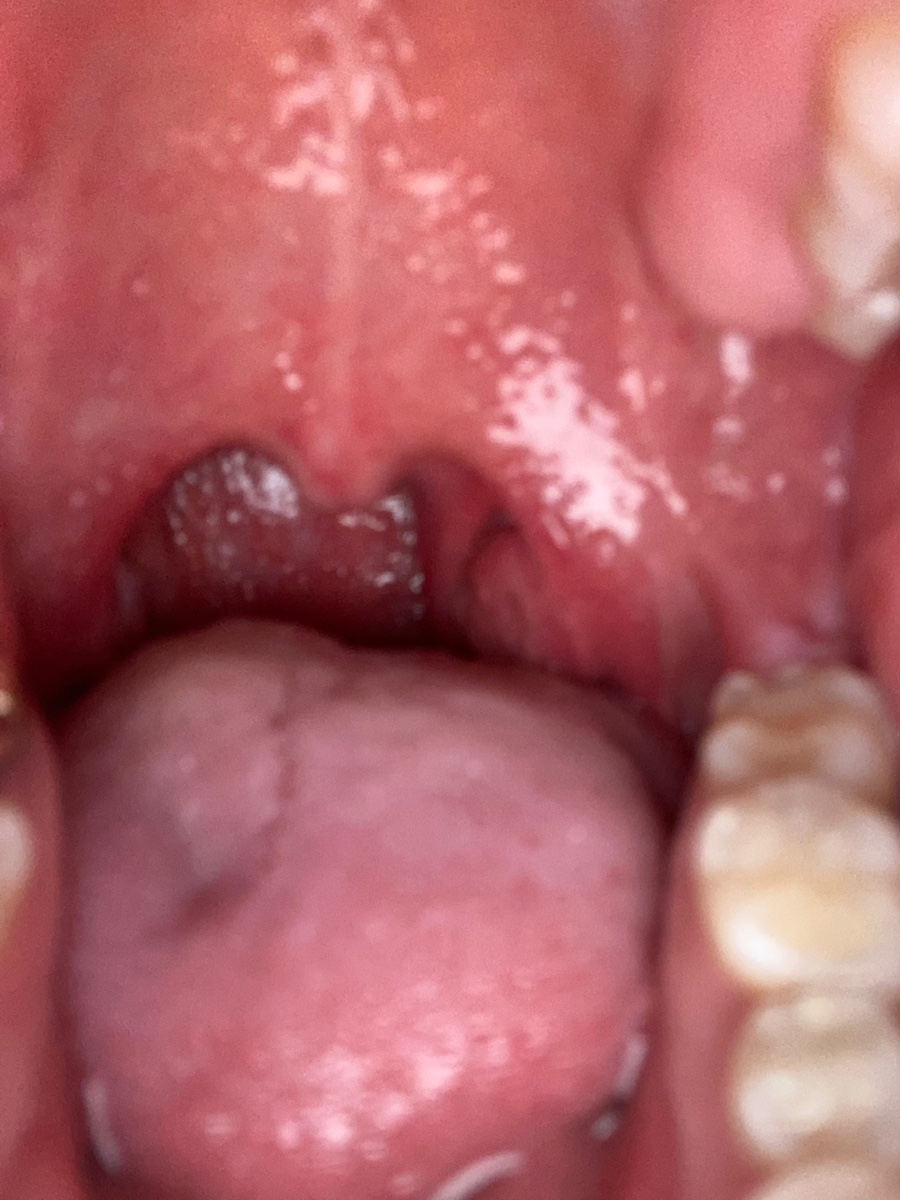

밤 9시경 편도 사진 최대치로 부은 모습.

아침을 먹고 아침 8시쯤 편도 사진 농양이 확실히 보이면 빨리 짜고 편해지고 싶다.. 이 생각만 했던거 같아서..